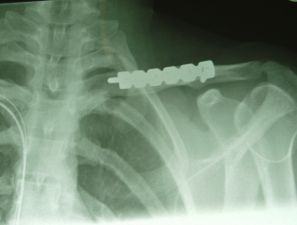

Forty nine patients were included in the

study. There were 22 patients in the anterior group (Fig 1) and

27 in the superior group (Fig 2). The mean age in the anterior

Fig.1

Fig.2